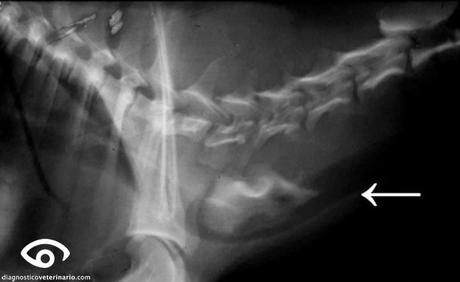

Aquí os dejo una foto de una radiografía de un perro al que se le quedó un hueso en el esófago y la foto del hueso de 6cm:

En éste caso, lo tuvieron que sacar por toracotomía (por el tórax) ya que la forma del hueso y tamaño no podía bajar hasta el estómago por sí solo.